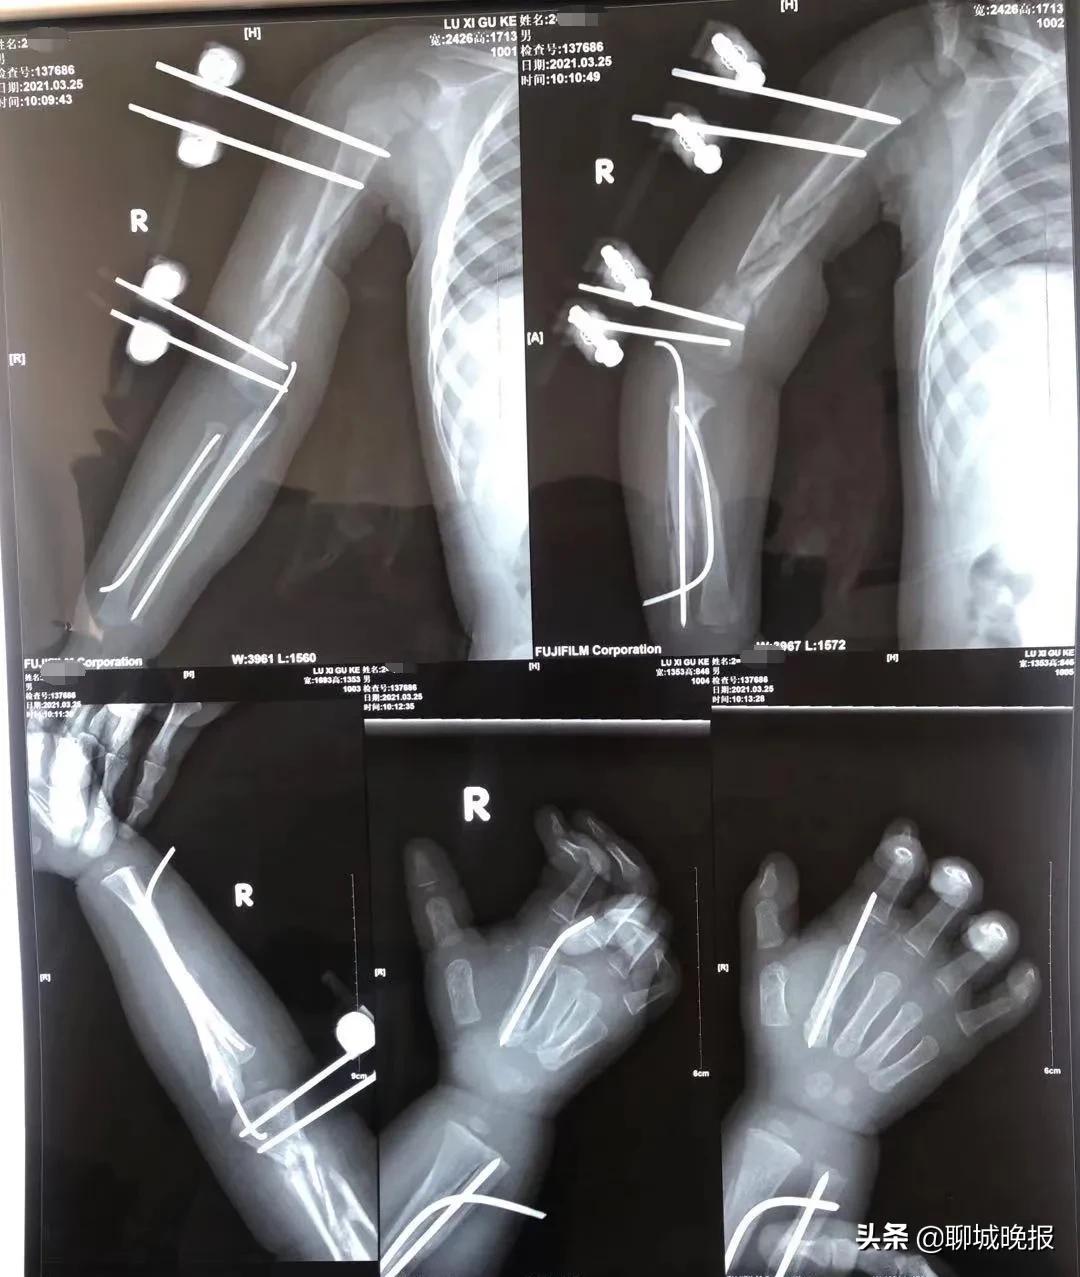

参考了各地骨科医生的建议后,鲁西骨科专家团队决定为患儿实施右肱骨干骨折复位外架外固定+右尺桡骨骨折小切口复位克氏针内固定+右第2掌骨骨折复位克氏针内固定术。

在征得家人同意后,王九现医生和刘玉钊医生成功为患儿实施了手术。术后,患儿的状态良好,家人对手术效果非常满意。

术前 ↑ 术后 ↓ 对比

这不,20天后,家人带患儿前来复查,受伤部位恢复良好,可以取出钢钉了。

“1岁9个月患儿多发骨折愈合良好,感谢张忠礼教授、邓书贞教授、王展教授以及各位的指导。”这个好消息,王书军主任分享到了微信群里,各地名医们由衷地为患儿的康复感到高兴,同时也为聊城骨科医院的高超治疗技术频频点赞。